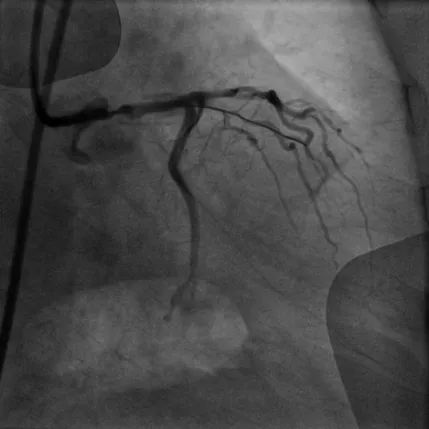

病例2

CTO病变:患者74岁男性,主因胸痛10余天,憋气1周余,加重2天入院,既往高血压、糖尿病病史、长期吸烟史。诊断急性非ST段抬高型心肌梗死、心力衰竭。强化用药改善心功能后择期行冠脉造影示LAD为CTO,RCA近段CTO病变、全程钙化影,圆锥支向LAD远端提供侧支循环。患者拒绝CABG治疗,决定开通RCA CTO。但患者RCA严重钙化,GW在微导管支持下通过CTO段,但应用普通球囊预扩后,无法送入IVUS导管,遂果断选择GuideZilla支持下Shockwave冲击波球囊治疗,成功植入支架,手术效果良好,为进一步解决LAD病变奠定了基础。